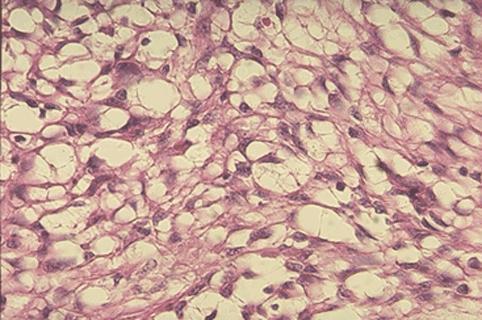

疾病(病理主体)的分类恶性非上皮性肿瘤/平滑肌肉瘤

部位(按器官分)小肠/空肠

检查方法病理切片(微观)

肿瘤最大直径40以上